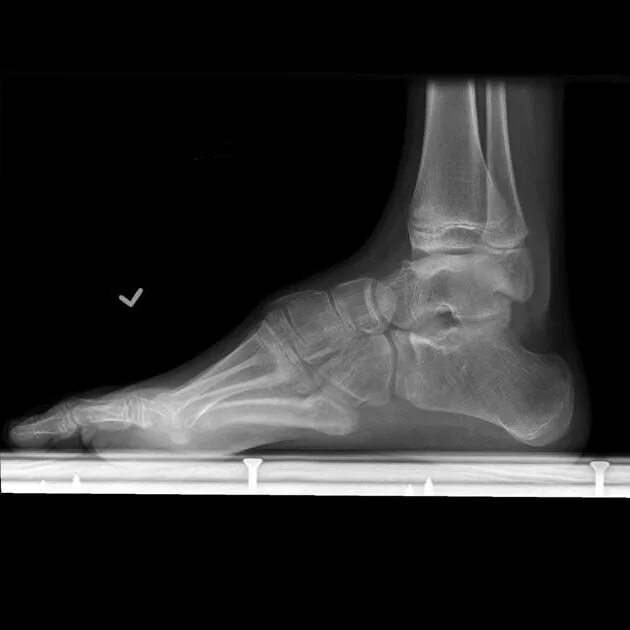

Продольное плоскостопие 2